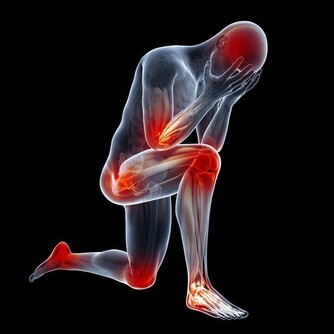

左臉頰長痘因為血液循環

左臉頰長痘說明你的血液排毒能力降低,有可能是肝臟出現了問題或是血液循環出現了問題。

建議:加速血液循環。不要讓身體處在悶熱中,可以用溫度略低於體溫的水洗澡,

多到戶外活動,吃一些涼血的食物,如絲瓜、冬瓜、柿餅、綠豆等。